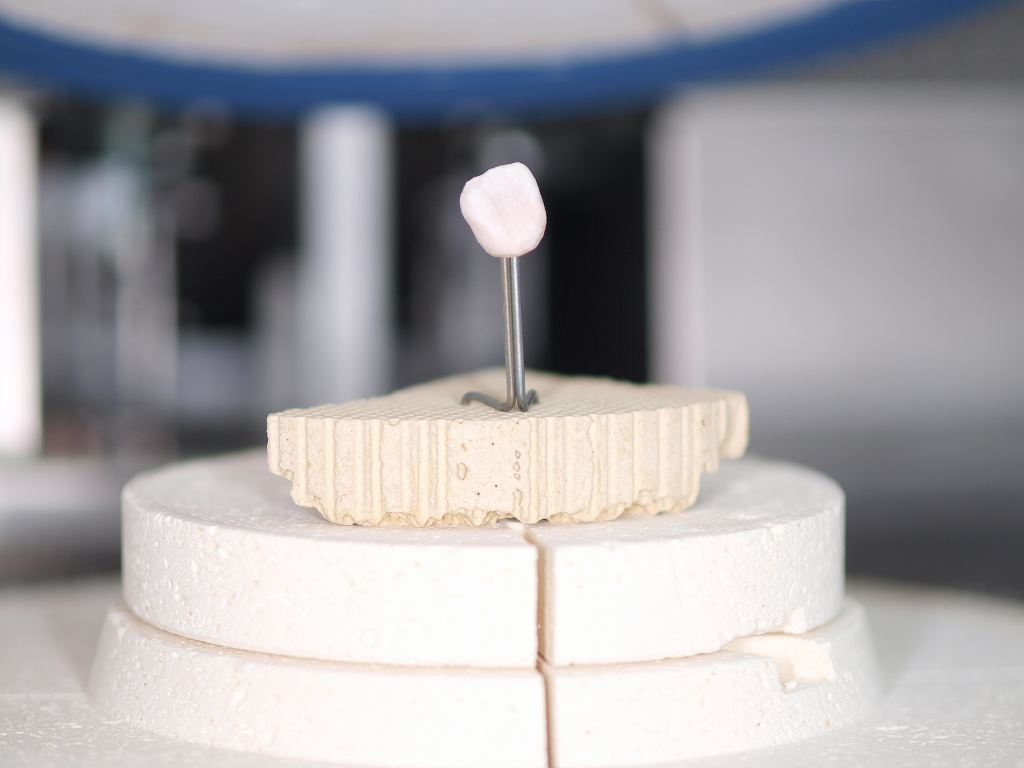

オールセラミックの削り出しになります

ポーセレンの築造をしては焼き上げています

ポーセレンの築造を焼成していきます